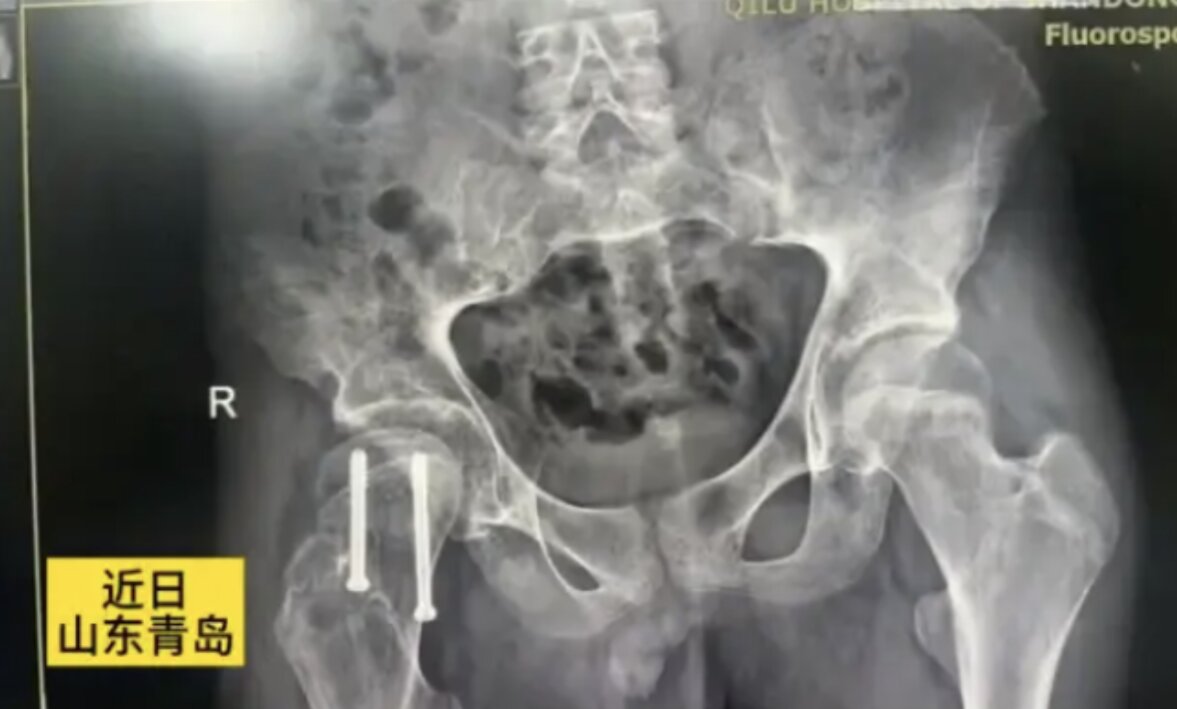

Anh Ai (38 tuổi, Thanh Đảo, Sơn Đông, Trung Quốc) đă trải qua một hành tŕnh sức khỏe đáng kinh ngạc. Dù chỉ cao chưa đến 1m60 khi 18 tuổi, anh bất ngờ cao thêm 20cm sau đó, đạt chiều cao 1m84. Tuy nhiên, đằng sau sự phát triển vượt bậc này lại là một căn bệnh hiếm gặp và phức tạp: Hội chứng đứt cuống tuyến yên kết hợp với chứng trượt đầu xương đùi.

Bên cạnh hội chứng đứt cuống tuyến yên, anh Ai c̣n mắc chứng trượt đầu xương đùi, một bệnh thường gặp ở thanh thiếu niên. Chứng bệnh này làm t́nh trạng sức khỏe của anh thêm phức tạp, gây đau đớn và hạn chế vận động.

Trượt đầu trên xương đùi (SCFE) là một t́nh trạng thường gặp ở vùng hông, chủ yếu xuất hiện ở thanh thiếu niên và thanh niên trong giai đoạn phát triển thể chất. Ở bệnh lư này, cổ xương đùi bị trượt lệch khỏi vị trí b́nh thường trên đầu xương đùi, hướng lên trên và ra trước, gây đau đớn, cứng khớp và làm suy giảm độ ổn định của khớp háng. T́nh trạng này thường tiến triển từ từ và có tỷ lệ mắc ở nam giới cao hơn so với nữ.

May mắn thay, anh Ai đă được phẫu thuật đóng đinh nội tủy rỗng để điều trị chứng trượt đầu xương đùi bên phải. Ca phẫu thuật đă thành công, giúp giảm đau đáng kể và cải thiện khả năng vận động cho anh. Tiên lượng sau phẫu thuật của anh được đánh giá là tốt.